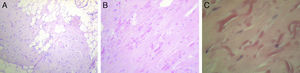

Case 4A 60-year-old with a history of osteoarthritis in the hands and thyroid nodules with hypothyroidism treated with levothyroxine consulted in January 2008 due to pain in the left subscapular region since one month earlier, which was increasing in size and spreading to the pectoral region, with limited movement of the left shoulder. Physical examination showed a painless mass of soft consistency with irregular margins of about 5cm in diameter but with painful restriction of left shoulder movement. Ultrasound of the area showed a heterogeneous solid formation of 2.5 by 4.5cm in diameter, with partially defined contours, while in the right subscapular region a solid, ovoid formation was observed, 2.5 by 1cm diameter, with homogeneous margins, which occupied the right subcutaneous plane. Hematological and biochemical analyzes were normal. In April 2008, the patient underwent surgery for the left lesion, it being a heterogeneous tumor, adhered to deep planes, ribs, and pleura. The pathologist described a proliferation composed of abundant dense collagen tissue of myxoid aspect, which included rare spindle cells with minimal nuclear irregularity and numerous fragmented elastic fibers intermingled with mature adipose tissue, consistent with elastofibroma dorsi (Fig. 3A–C).